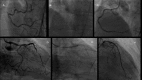

Robotic technology has been used in cardiovascular medicine for over a decade, and over that period its use has been expanded to interventional cardiology and percutaneous coronary and peripheral vascular interventions. The safety and feasibility of robotically assisted interventions has been demonstrated in multiple studies ranging from simple to complex coronary lesions, and in the treatment of iliofemoral and infrapopliteal disease. These studies have shown a reduction in operator exposure to harmful ionizing radiation, and the use of robotics has the intuitive benefit of alleviating the occupational hazard of operator orthopedic injuries. In addition to the interventional operator benefits, robotically assisted intervention has the potential to also be beneficial for patients by allowing more accurate lesion length measurement, stent placement, and patient radiation exposure; however, more investigation is required to elucidate these benefits fully.